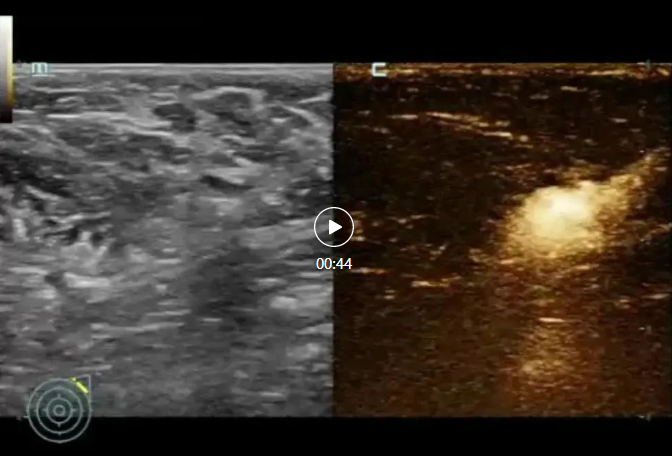

那么如何进行准确的前哨淋巴结定位呢?超声造影和超声引导下前哨淋巴结染色是各不错的选择。目前应用较多的染色剂有两种,术中应用“亚甲蓝”染料,超声引导下通常使用核素染色法进行术前一天定位染色,术中使用伽马探测仪找出核素热点的淋巴结进行病理检查。

设备要求:具备高质量超声造影技术的高端超声设备 ;设置前哨淋巴结造影成像模式;